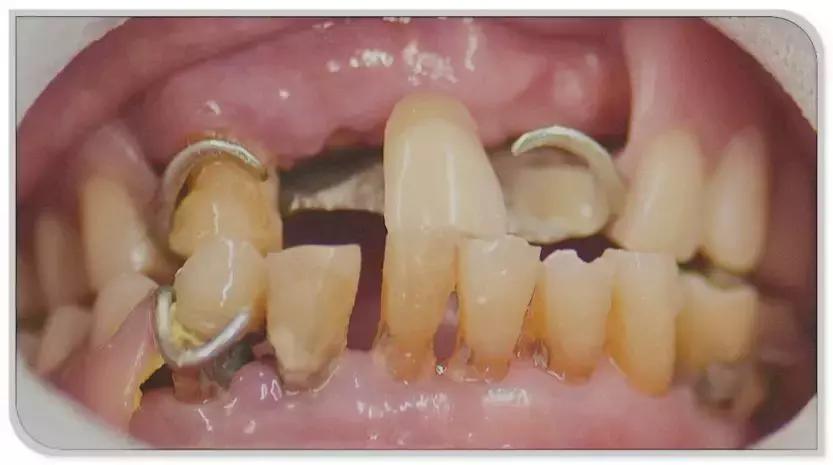

这就我妈治疗前口内的情况,很糟糕

挂钩假牙一戴就是十几年,期间换了5、6副假牙,慢慢的把旁边的牙都给挂松了,陆陆续续又掉了几颗槽牙,还有牙周炎和龋齿,有些牙烂了只剩下牙根,一口牙就没剩下几颗好牙了。

这两年她老说假牙挂的牙床子疼,吃不了饭,顿顿稀饭面汤,吃菜基本都不怎么嚼,整个吞下去,什么菜都要煮烂蒸熟了吃,没营养人也消瘦的很。